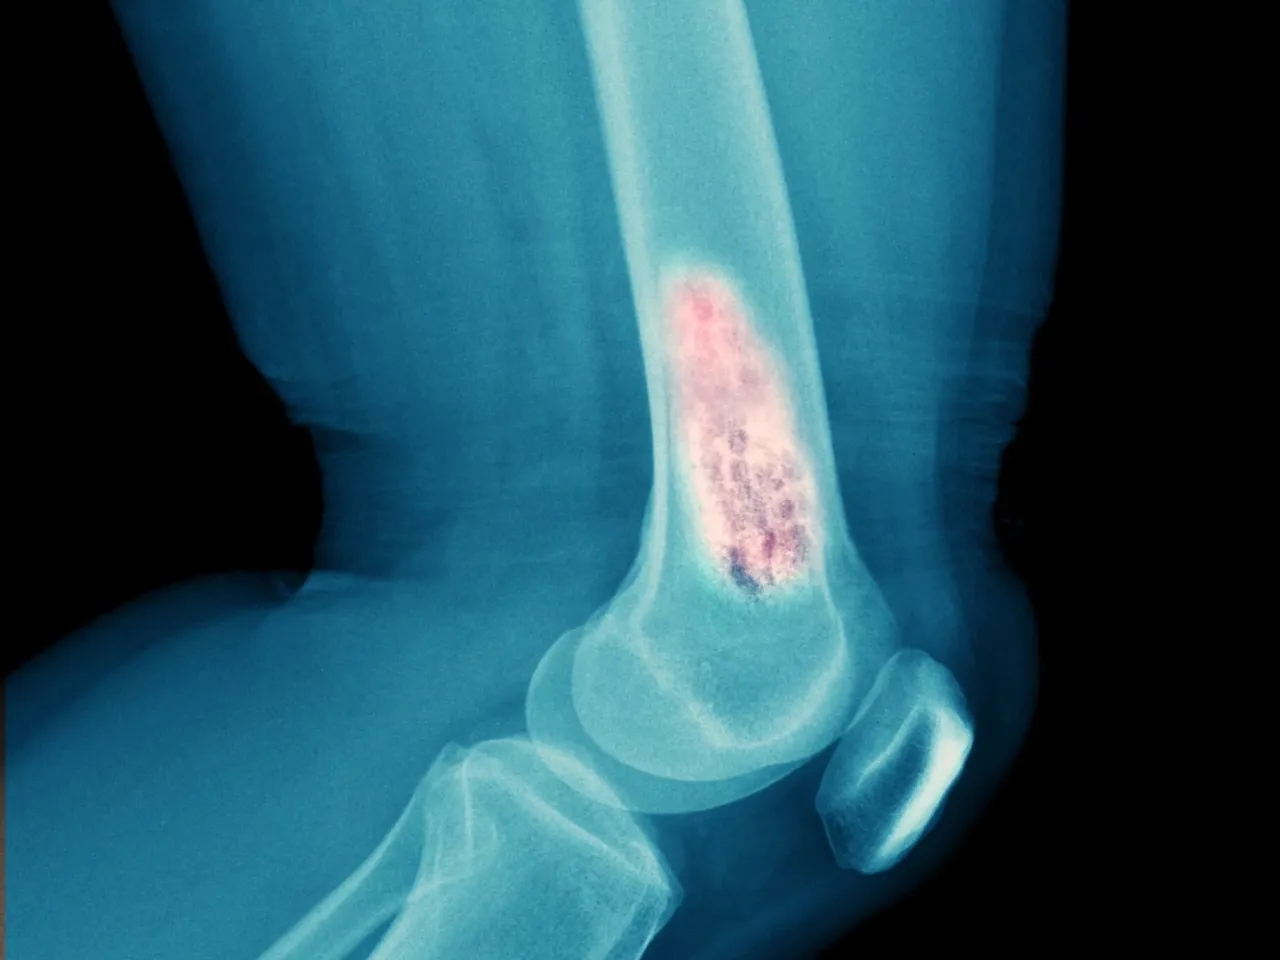

Złamania patologiczne: Kiedy kość pęka bez wyraźnego powodu?

Przerzuty do kości osłabiają jej strukturę, czyniąc ją niezwykle podatną na uszkodzenia. W efekcie może dojść do tzw. złamań patologicznych. Są to złamania, które występują przy niewielkim urazie (np. upadek z wysokości własnego ciała) lub nawet samoistnie, bez żadnej wyraźnej przyczyny. Pojawienie się takiego złamania jest zawsze alarmującym sygnałem i wymaga pilnej diagnostyki w kierunku przerzutów.

- Kości udowe i kości ramienne: W tych długich kościach również często pojawiają się zmiany.